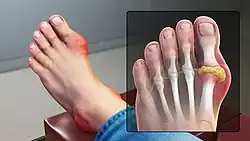

Gouty tophus of the left metatarsophalangeal joint, causing hallux valgus -

Gout in the big toe of the left foot, compared to the healthy right foot -

Gout in the joint of the big toe -